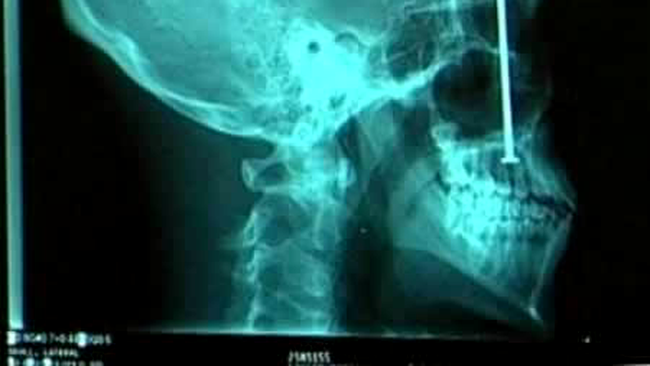

Cele mai ciudate obiecte descoperite la radiografii (Poze)

Radiologii raman uimiti cand vad in radiografia unui pacient obiecte care in mod obisnuit nu ar trebui sa se afle acolo.

Cazurile in care o persoana si-a batut un cui in cap sau in ochi, si-a introdus o sticla in anus sau a inghitit chei sunt uimitoare chiar si pentru doctori.

Medicii radiologi raman muti de uimire cand vad in radiografia unui pacient obiecte care in mod obisnuit nu ar trebui sa se afle acolo.